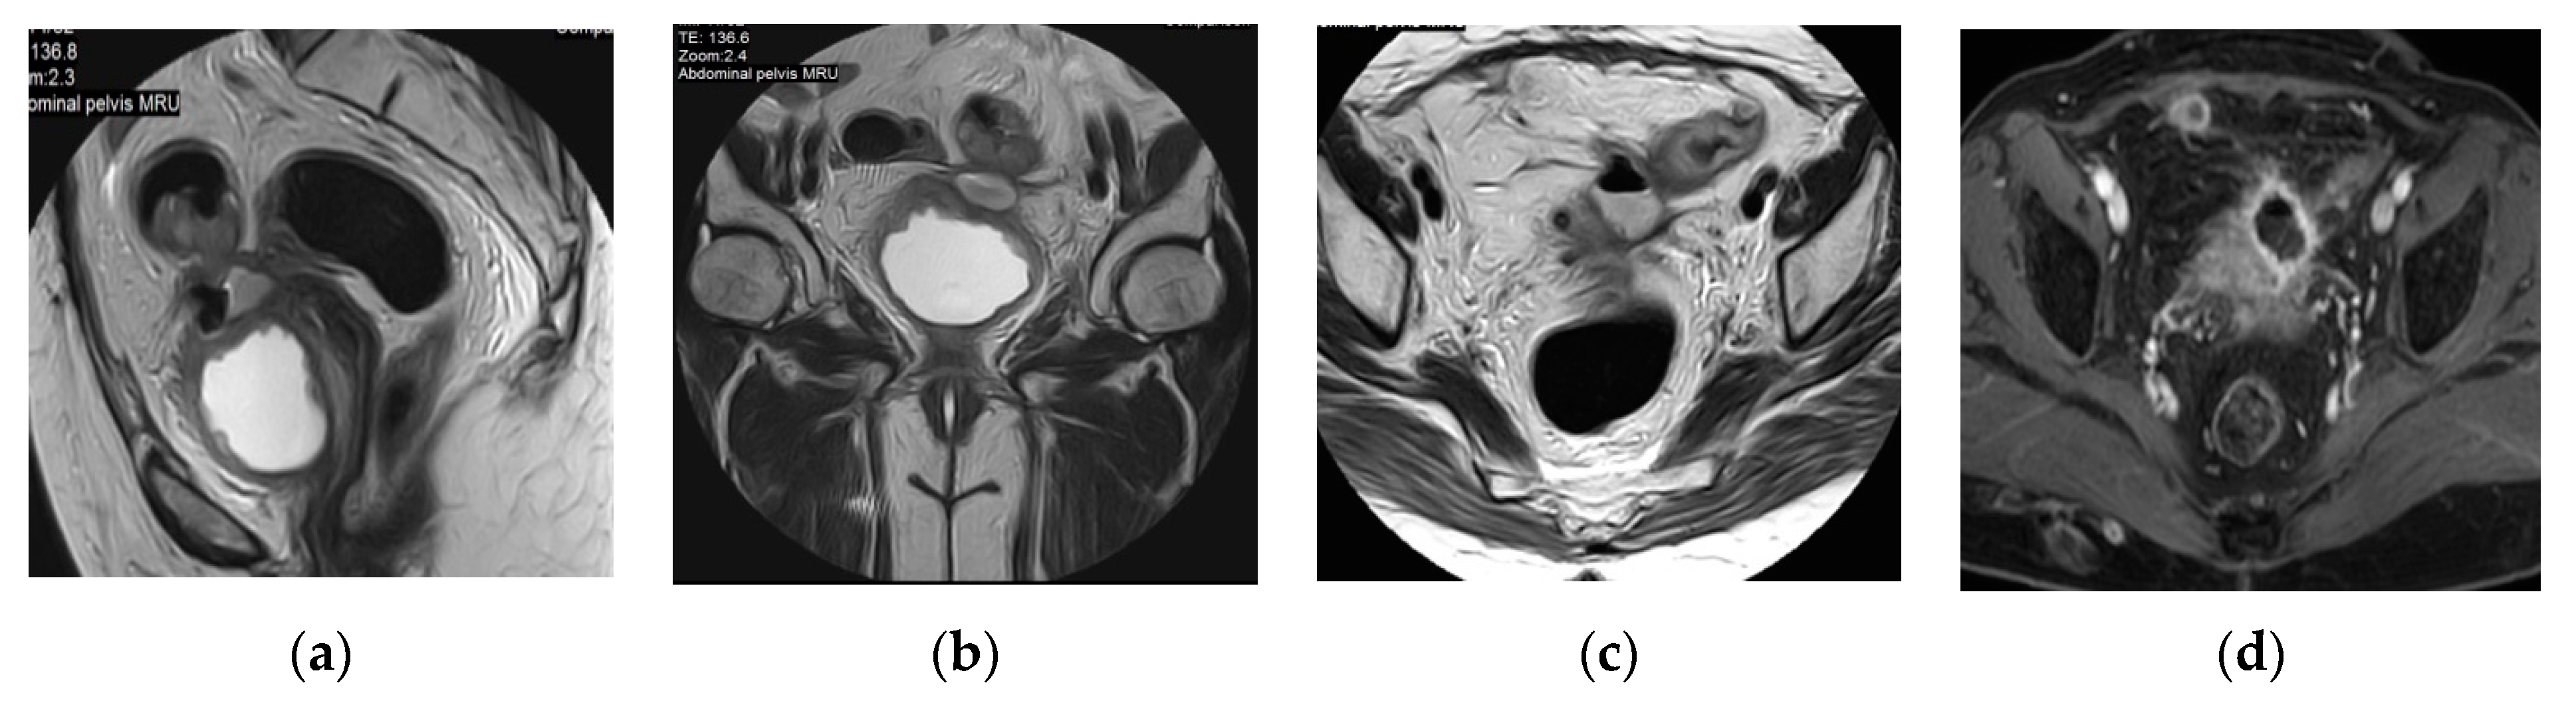

2.3. Pyonephrosis

| Pyonephrosis | Dilated thick-walled hyperenhancing collecting system, distended with high attenuation pus-filled fluid, fluid—fluid layering at T2WI, and thinning of the renal cortex. |